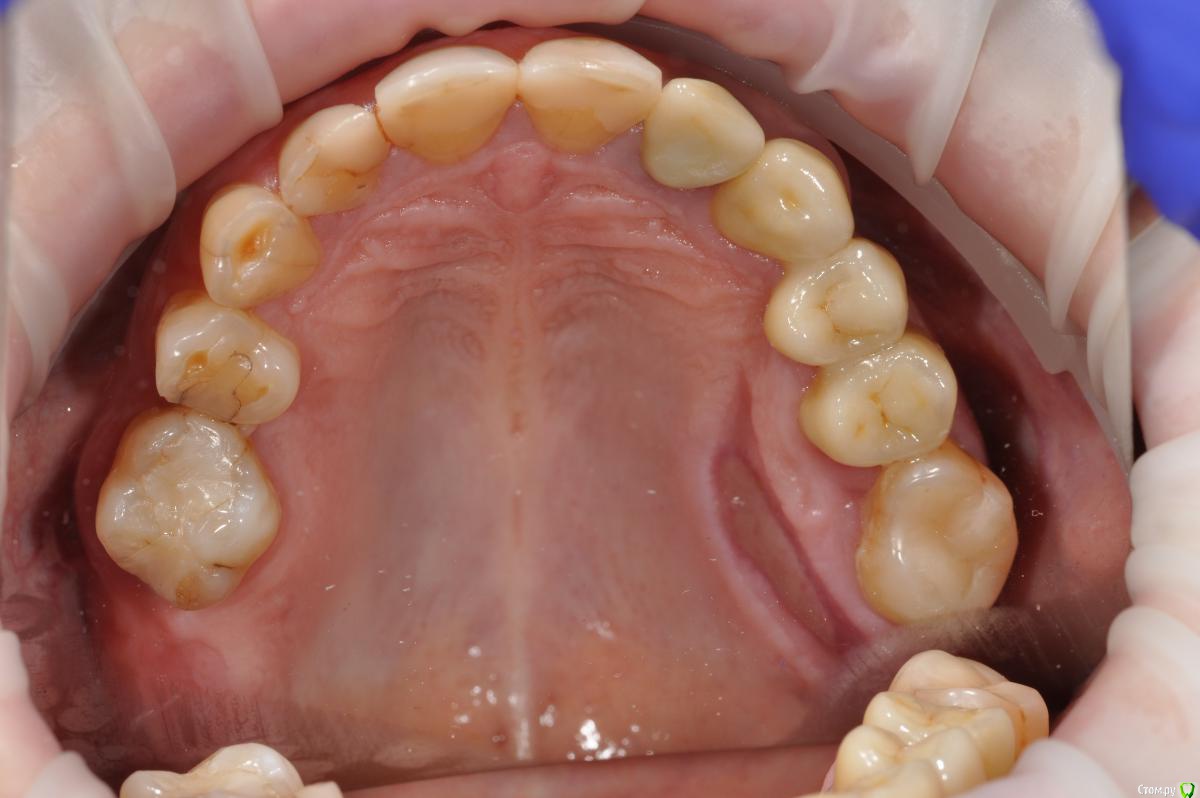

Большой Зеленый Опубликовано 16 ноября, 2018 Поделиться Опубликовано 16 ноября, 2018 Протезирование помогает.Была пациентка .И чего я только ей не делал...После постановки короткого формирователя стало немного лучшеБыло решено запротезировать.Помогло 6 Ссылка на комментарий

Neilrus Опубликовано 16 ноября, 2018 Поделиться Опубликовано 16 ноября, 2018 Отсеки слизистую и подшей ниже будто сдт собираешься подсадить. С подворотом. Из сом сделай гребень. Клеить и к фдм и к зубам рядом если есть. Надо фото найти... Господа, Как вы решаете вопрос с отсутствием зкпд в полном обьеме.у пациенки жалобы на то что" при поднятии языка, дна полости рта поднимается и нализиет на формирователь десны, соответственно на протезирование я пока не хочу передавать.в течении 3 недель у пациентки выросла шишка под языком в области 3 6 зуба...убрал формирователь и поставил заглушку.Видел у Ильгама как он делал зкпд, не скинете видео? не могу найтии что делать с этой шишкой и как вести пациента? спасибодумаю до надкостницы расщепитесь со стороный переходной, подшейте как можно ниже, а к самой надкостнице полнослойный как можно плотнее пришейте, без фдм будет лучше, их потом, Каппу не забудьте на небо заранее, ибо кусочек будет нормальный.Почти похожий случай, фоткиприкрепил, не судите строго, выкладываюсь редко, прикрепленки было 1,5-2мм и то язычно 2 Ссылка на комментарий

Neilrus Опубликовано 16 ноября, 2018 Поделиться Опубликовано 16 ноября, 2018 (изменено) что-то они в обратно порядке залились..ваще опыта нет (конец вот такой: Изменено 16 ноября, 2018 пользователем Neilrus Ссылка на комментарий